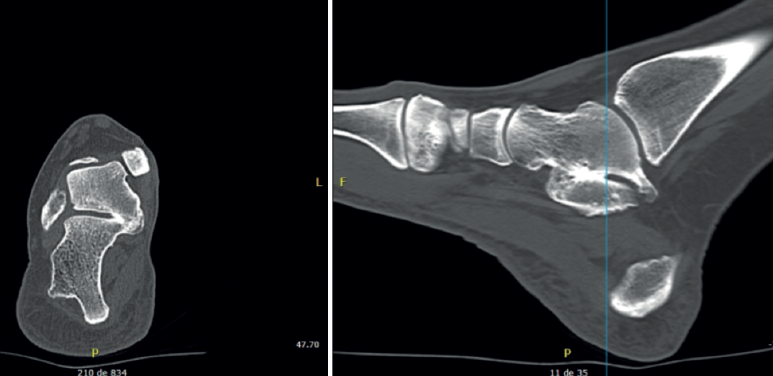

Ante la presencia de alguno de los signos previamente descritos, asociado con una clínica sugerente, debemos sospechar la existencia de una coalición tarsiana. Si hay confirmación con las radiografías simples, una TAC puede ser la prueba de elección. Es una herramienta fundamental para confirmar el diagnóstico y permite describir la localización y el tamaño de la coalición, así como planificar el tratamiento. Además, permite obtener una valoración del estado de la articulación objetiva y descartar la presencia de otras coaliciones concomitantes. Sin embargo, la TAC puede tener sus limitaciones en los casos de coaliciones no óseas: en 100 pies disecados, Solomon et al.(49) encontraron 9 fusiones no óseas TC o CN, de las cuales solo el 55% habían sido correctamente detectadas por la TAC. Más aún cuando 4 sospechas de coalición no fueron a posteriori confirmadas por la disección.

En caso de sospecha sin confirmación radiológica, podríamos valorar una RM, que facilita la detección de coaliciones cartilaginofibrosas con una alta sensibilidad sin exponer al paciente a tasas de radiación (sobre todo en pacientes en edad pediátrica). La RM se muestra de gran ayuda en casos de traumatismo asociado a una coalición. Permite evaluar otros lugares como potenciales fuentes del dolor: roturas ligamentosas, lesiones osteocondrales o patología tendinosa, entre otros. Independientemente de la localización de la coalición, en caso de fibrocartilaginosas se apreciará edema de las facetas(50). Sin embargo, en el caso de uniones óseas puede haber falsos negativos, precisando exámenes exhaustivos con suficiente resolución. En la práctica, permite ver signos indirectos de sufrimiento de las articulaciones periféricas por adaptación, sobre todo a nivel de la Chopart. Algunos autores hablan de superioridad diagnóstica de la RM, calificándola de técnica de elección(50,51,52). En un estudio con 19 pacientes con fisis abiertas, determinan que la RM con gadolinio identifica todas las coaliciones, frente a la TAC, que no detecta 4 casos.